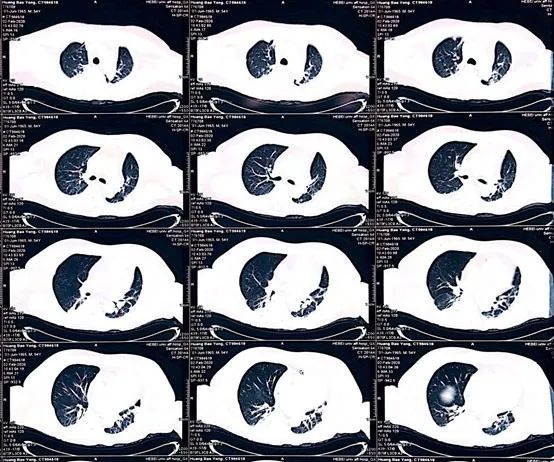

胸部CT:双肺散在炎症,食管裂孔疝。

图3. 胸部CT影像。

急请肿瘤内科会诊,肾癌患者应用免疫*制剂抑**特瑞普利单抗后出现双侧眼睑下垂、气短、胸闷,诉肢体乏力,心电图示三度房室传导阻滞,心肌三项增高,NT-proBNP增高。患者肾尿路上皮癌术后辅助化疗,PD-L1*制剂抑**治疗两周期,出现喘憋、气短,心电图及心肌酶急性进展表现。胸部CT示双肺散在炎性改变。

图6. 胸部、腹部、头颅CT扫描(2020-02-02):可见两肺散在炎症、双侧胸膜增厚、食管裂孔疝;与2020-01-31影像比较,双肺炎症加重,双侧胸膜新发增厚。颅脑CT平扫未见异常,肝右叶后下段囊肿。

(5)患者咳少量白痰,双肺散在炎症,复查胸部CT示双肺炎症加重,双侧胸膜新发增厚,白细胞增高,C反应蛋白增高,降钙素原正常。